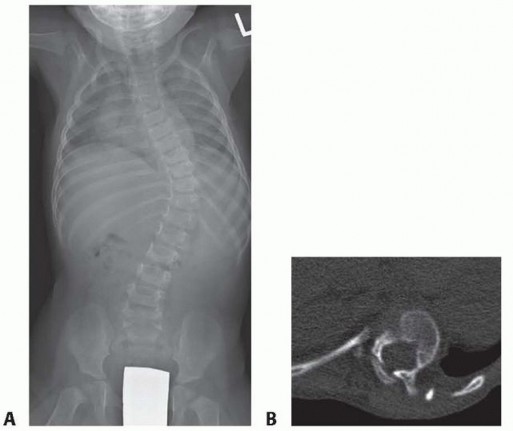

Dystrophic scoliosis is the most aggressive and challenging variant. It is characterized by a short-segment, sharply angulated curve. Radiographically, dystrophic curves present with a constellation of severe structural anomalies:

* Severe wedging of the apical vertebral bodies.

* Extreme axial rotation of the vertebrae.

* Posterior scalloping of the vertebral bodies (often secondary to dural ectasia).

* Spindling (thinning) of the transverse processes.

* Enlargement of the neural foramina.

* "Penciled ribs": Rotation of the ribs 90 degrees in the anteroposterior direction, making them appear abnormally thin and dysplastic.

Curves with significant sagittal plane deformity are highly prevalent in dystrophic scoliosis. Neurofibromatosis kyphoscoliosis is particularly notorious, characterized by acute, rigid angulation in the sagittal plane and striking destruction or deformity of the vertebral bodies near the apex. Severe thoracic lordoscoliosis has also been documented by Winter, presenting unique respiratory and biomechanical challenges.

The preoperative workup for an NF-1 patient with spinal deformity must be exhaustive. The presence of intraspinal lesions—such as pseudomeningoceles, dural ectasia, or intraspinal neurofibromas (dumbbell tumors)—must be definitively ruled out before any surgical instrumentation is attempted.

Routine total spine Magnetic Resonance Imaging (MRI) is mandatory. Ramachandran et al. demonstrated that 37% of NF-1 patients (in both dystrophic and nondystrophic groups) harbored intraspinal and paraspinal neurofibromas, often adjacent to the convexity of the curve. While MRI is superior for evaluating cord displacement and the subarachnoid extent of neurofibromas, severe kyphoscoliotic deformities may render MRI inadequate due to artifact and complex multi-planar anatomy. In such cases, complete high-volume CT myelography in the prone, lateral, and supine positions is required to accurately map the spinal canal.